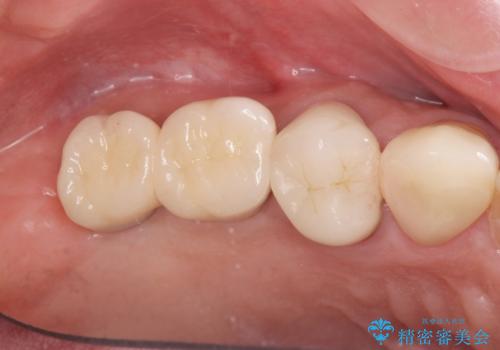

- 88万円(インプラント×2・仮歯×2・チタンカスタムアバットメント×2・ジルコニアクラウン×2)費用は治療当時の料金となります

またしっかりと噛めるようになり、食事を楽しめるようになった!と喜んでいただくことができました。